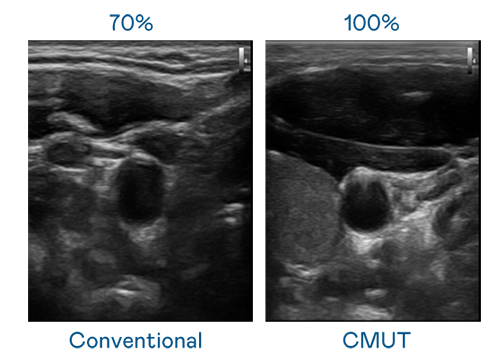

CMUT 技術是一種用電容式微機電元件來產生超音波訊號的技術。與傳統 PZT 壓電式技術相比,CMUT 頻寬增加 30%,更寬頻的超音波訊號讓影像解析度大幅提升,是實現高影像品質醫療超音波掃描、促進精準醫療發展的關鍵技術。

大頻寬帶來超清晰影像

超音波影像的解析度高低,首先取決於探頭能發出的訊號頻寬。南宫·28WD CMUT 可提供高清晰的超音波訊號,提供高頻寬、高靈敏度、影像紋理細節更高的超音波影像,協助醫護人員縮短影像判讀時間及利用精準的醫療影像進行診斷。